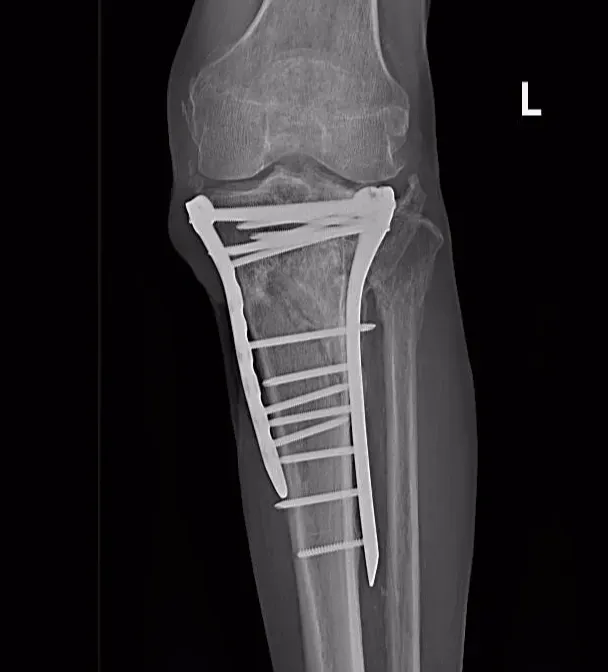

术前

术后